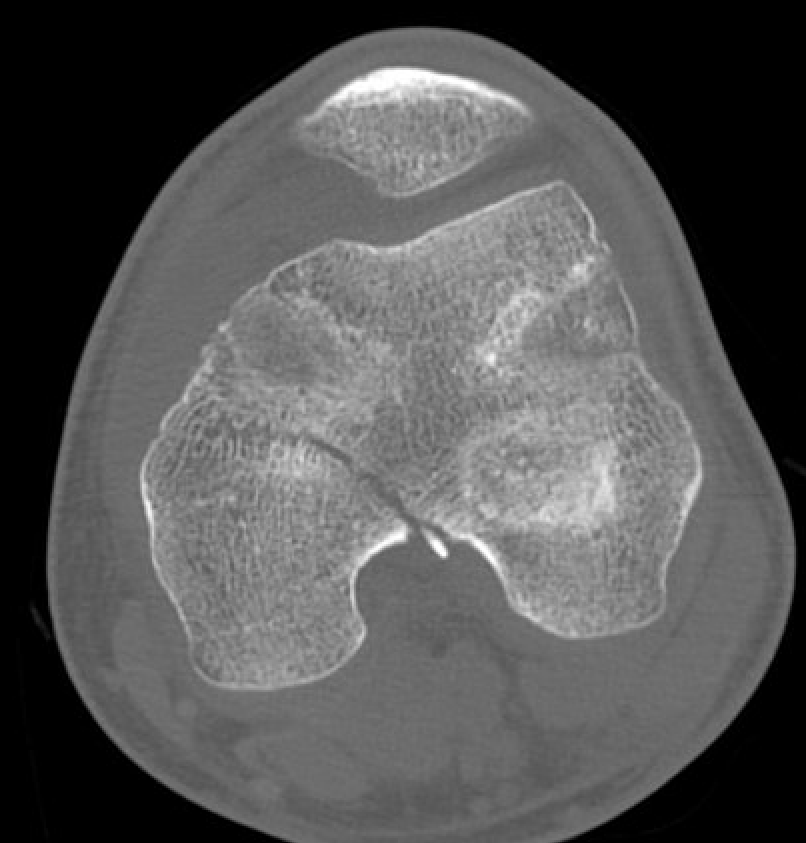

SH2Dis femurDis femur

Management

CT / MRI - assess percentage of bony bridge

Bony bridge < 50%

- excision and fat graft

- manage angular deformity with 8 plates / osteotomy

Bony bridge > 50%

- hemi-epiphysiodesis

- may need later correction of LLD and angular deformity